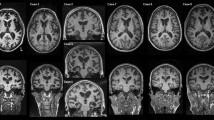

Microscopic comparison of AD pathology in two C9ORF72 mutation carriers presenting with pathological AD (Case 24: a, c; Case 10: b, d). Cases stained with a tau antibody (PHF-1; a, b) and an Aβ antibody (33.1.1; c, d). Red inserts show ×5 magnification of the hippocampus endplate, dentate fascia, and molecular layer. Blue inserts show ×5 magnification of the inferior temporal cortex. Case 24 has abundant tau and Aβ pathology in the hippocampus and temporal cortex consistent with Braak Stage V (a, c). While Case 10 has less overall tau and Aβ pathology in comparison to Case 24, the distribution of tangles is consistent with a similar Braak Stage V–VI (b, d). Insert bar 100 μm

Immunofluorescence in the hippocampus of a pathological AD case. a Double stain with Ubqln2 and phospho-tau (PHF-1) reveals comorbidity of C9ORF72 pathology (neurites and NCIs) and AD pathology (plaques and tangles) with minimal colocalization. b Double stain with ubiquilin 1 (Ubqln1), a known marker of tangles, and Ubqln2 reveals co-labeled NCIs which could reflect sequence homology between the ubiquilins and poor antibody epitope specificity. While there are co-labeled puncta swellings in the molecular layer neurites, Ubqln1 does not label the entire process. Additionally, Ubqln1 labels a potential tangle in the dentate fascia; however, this neuron is also marked by Ubqln2 which is not known to stain tangles (Case 24, ×10 magnification)